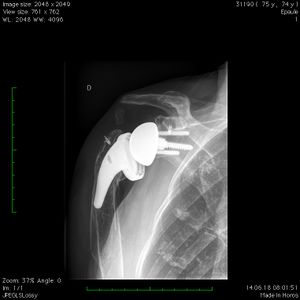

The distalization shoulder angle (DSA) angle is formed by a line connecting the most lateral border of the acromion and the superior glenoid tubercle and a line connecting the superior glenoid tubercle and the most superior border of the greater tuberosity. In this case, it is measured at 61 degrees.

The lateralization shoulder angle is formed by a line connecting the superior glenoid tubercle and the most lateral border of the acromion and a line connecting the most lateral border of the acromion and the most lateral border of the greater tuberosity. In this case, it is measured at 77 degrees.